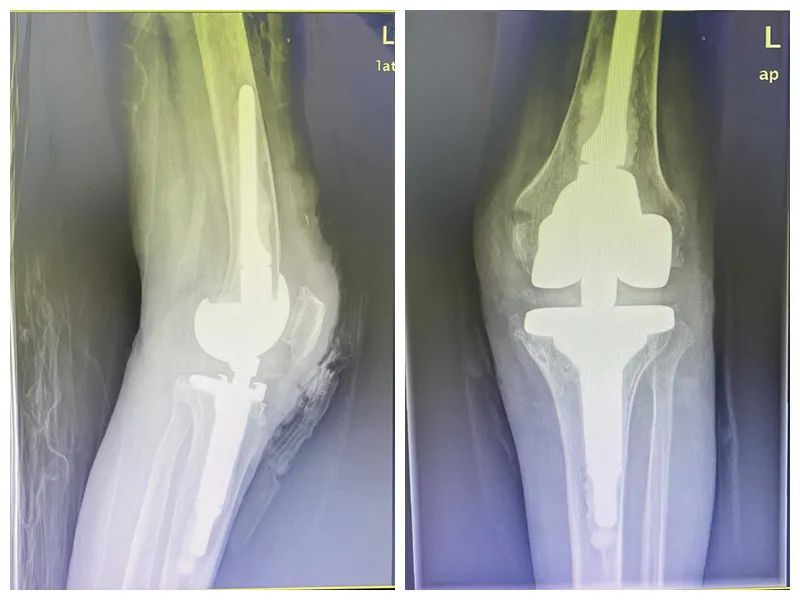

▲患者术后影像

结合患者入院后膝关节CT及膝关节MRI。诊断为左侧膝关节重度骨性关节炎伴膝关节脱位、类风湿性关节炎,考虑到患者双膝疼痛已久,严重影响生活和工作,迫切希望投入到生活中。在大外科主任陈子华指导下,关节外科和运医学科主任曾红生带领关节外科团队经讨论后,决定全麻下为该患者施行铰链式人工膝关节置换术,精确植入铰链式膝关节假体。整个手术过程顺利,术后被安全地送回病房进行恢复。

铰链式人工膝关节置换术是一种用于治疗重度膝关节疾病的手术方式,特别适用于因退行性膝关节病变、类风湿性关节炎、创伤性关节炎等原因导致的膝关节退变伴有脱位的关节功能障碍。该手术通过置换受损的膝关节部分,使用人工关节假体来恢复膝关节的功能。铰链式膝关节假体能够使患者在手术后能够较快地恢复日常活动。有助于患者在术后保持较好的生活质量。特别适用于那些因复杂病变(如韧带断裂、骨缺损等)而无法进行常规膝关节置换的患者。